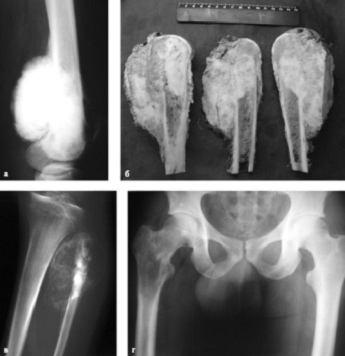

Биопсия - это забор образца ткани с целью ее последующего изучения под микроскопом. Это единственный способ выявить злокачественность опухоли. При наличии рака биопсия подскажет врачу, является ли опухоль первичной или представляет собой метастаз. Для диагностики злокачественных опухолей костей используется несколько образцов тканей и клеток (рисунок 3)

рисунок 3